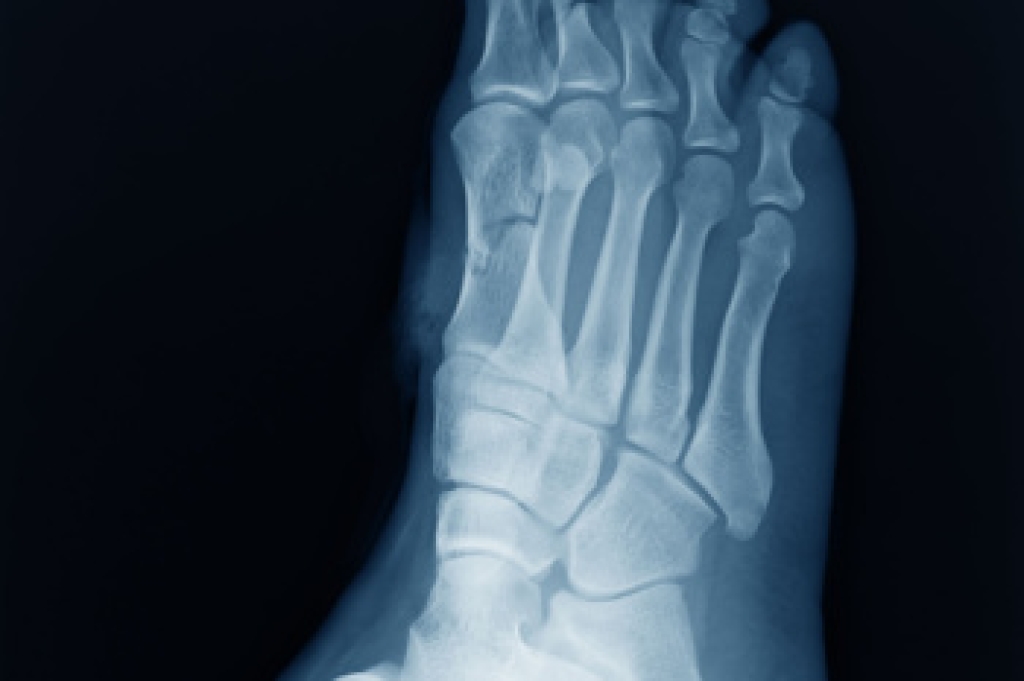

Sever’s disease is also known as calcaneal apophysitis, which is a medical condition that causes heel pain I none or both feet. The disease is known to affect children between the ages of 8 and 14.

Sever’s disease occurs when part of the child’s heel known as the growth plate (calcaneal epiphysis) is attached to the Achilles tendon. This area can suffer injury when the muscles and tendons of the growing foot do not keep pace with bone growth. Therefore, the constant pain which one experiences at the back of the heel will make the child unable to put any weight on the heel. The child is then forced to walk on their toes.